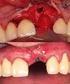

2 Implantation Die Stabilität entscheidet Kierferkammatrophie Knochenabbau nach Zahnverlust Die wichtigste Voraussetzung um ein Implantat sicher und mit langfristigem Erfolg setzen zu können, ist das Vorhandensein eines ausreichenden Knochenvolumens. Wenn der vorhandene Knochen aufgrund eines Rückgangs des Kieferkammes nicht ausreicht, muss Knochen aufgebaut werden, um ein Implantat stabil einsetzen zu können. Diese Situation ist vergleichbar mit dem Einsetzen eines Dübels in eine sehr dünne Wand; er wird nicht genügend Halt finden. In vielen Fällen kann man nach einem länger zurückliegenden Zahnverlust oder dem langjährigen Tragen von Prothesen eine Rückbildung des Kieferknochens (Kieferkammatrophie) beobachten. Unser Knochen ist ein dynamisches Gewebe, er wird dort verstärkt gebildet, wo er viel benötigt und beansprucht wird. Andererseits wird er allerdings auch dort abgebaut, wo eine Belastung fehlt. Im gesunden Kiefer übertragen die Zähne beim Kauen einen Druck auf den Knochen und geben damit ein Signal für dessen Erhalt. Nach einem Zahnverlust fehlt dieser Kaudruck und der Knochen bildet sich nach und nach zurück. In solchen Fällen muss vor dem Einbringen von Implantaten der Kieferknochen wieder aufgebaut werden. Neben vielen funktionellen und ästhetischen Vorteilen eines implantatgetragenen Zahnersatzes besteht ein wichtiger Vorteil auch darin, dass die Implantate den Kaudruck auf den Knochen überleiten und damit zu dessen Erhalt beitragen.

3 Knochenaufbau Regeneration von verlorengegangenem Knochenvolumen In mehr als der Hälfte der Fälle ist heute, für das optimale Setzen von Implantaten, ein zusätzlicher Knochenaufbau notwendig. Wenn die Höhe und Breite des Restknochens ausreichend ist, kann das Implantat eingeschraubt und gleichzeitig der Knochen herum aufgebaut werden (einzeitiges Vorgehen). Wenn der Restknochen nicht ausreicht um ein Implantat primärstabil zu setzen, muss zunächst der Knochen aufgebaut werden. Die Implantate können dann erst nach einer bestimmten Heilungszeit gesetzt werden (zweizeitiges Vorgehen). Für den Knochenaufbau kann der Implantologe Knochen in Form von Blöcken oder Knochenspänen aus verschiedenen Bereichen der Mundhöhle entnehmen (z.b. zahnlose Bereiche, Kieferwinkel, Kinn) und diesen in das Aufbaugebiet einbringen. Zwar ist der eigene Knochen aus biologischer Sicht das optimale Material zum Aufbau, seine Verwendung birgt allerdings auch einige Nachteile. Zum einen steht dieser Knochen nur in begrenztem Umfang zur Verfügung. Außerdem erfordert die Entnahme von Eigenknochen oft die Eröffnung eines zweiten Operationsgebietes und ist daher verbunden mit größeren Schmerzen sowie einem erhöhten Infektions- und Komplikationsrisiko nach dem Eingriff. Daher wurden verschiedene Knochenersatzmaterialien zum Wiederaufbau (Regeneration) von verlorengegangenem Knochenvolumen entwickelt.